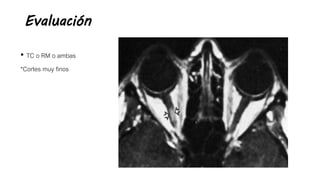

Evaluación

• TC o RM o ambas

*Cortes muy finos